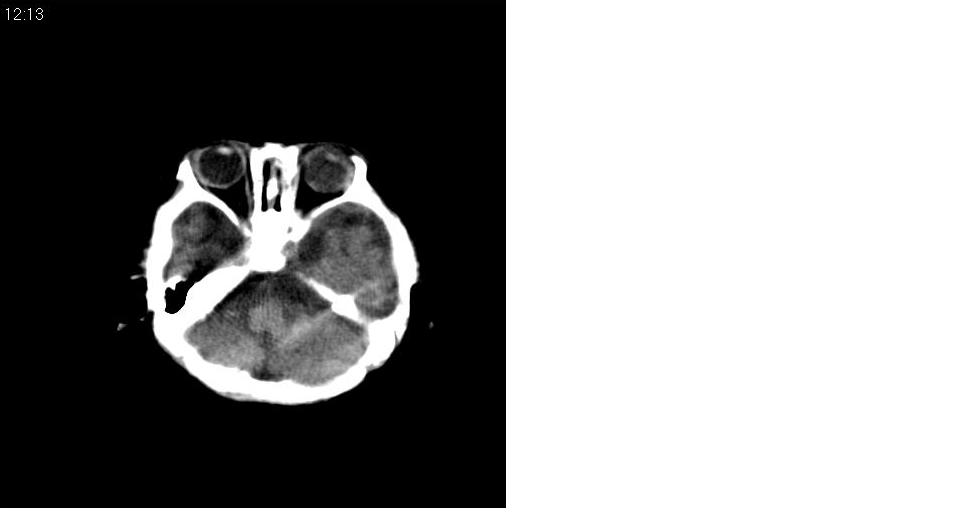

标题: PED1744:颅脑CT平扫

男 3个月,头大,颈软,头向后仰。

外部性脑积水

考虑外部性脑积水。

脑外间隙增宽,未见明显异常。

脑外间隙增宽,余未见明显异常。

脑外间隙增宽,现在好像有人说是一种发育性的交通性脑积水

蛛网膜增宽,外部性脑积水?

外部性脑积水(也就是诸位说的脑外间隙增宽);脑实质内未见异常密度灶,脑室系统无扩张,建议随访,毕竟临床症状听着怪吓人的。